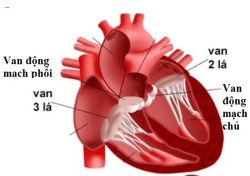

Bệnh van tim xảy ra khi một trong bốn van tim không hoạt động đúng cách, tức là không thể mở hoặc đóng hoàn toàn. Khi có triệu chứng hoặc yếu tố nguy cơ gây bệnh, việc sàng lọc bệnh van tim thông qua siêu âm tim hoặc các xét nghiệm khác là rất cần thiết.

Teo van động mạch phổi là một dạng dị tật bẩm sinh, trong đó van động mạch phổi (van tim nằm giữa tâm thất phải và động mạch phổi) không hình thành mà thay vào đó tim được ngăn cách với động mạch phổi bởi một lớp mô rắn. Teo van động mạch phổi thường được phát hiện ngay sau khi sinh.